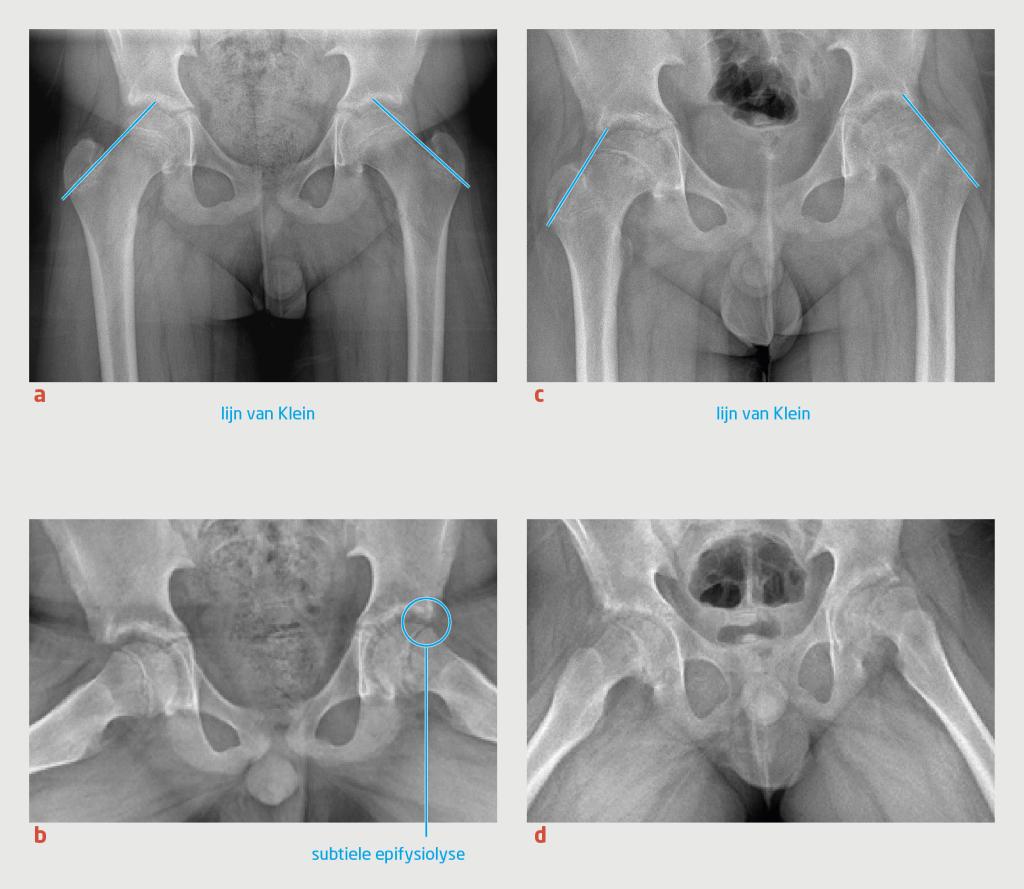

Patiënt D is een 12-jarige jongen die de huisarts bezocht, omdat hij sinds een aantal weken pijn in de linker lies ervoer. Patiënt had een opvallend mankend looppatroon, waarbij hij zijn linker been ontzag. Bij lichamelijk onderzoek was endorotatie van de linker heup beperkt. Hij had geen koorts. De huisarts liet röntgenopnames van het bekken maken, inclusief een anteroposterieure en een Lauenstein-opname (figuur 4). De radioloog beoordeelde deze beelden als niet afwijkend, waarop de huisarts de diagnose ‘tendomyogene klachten’ stelde.

Figuur 4

Progressie van de epifysiolyse van het caput ossis femoris bij een 12-jarige jongen

Figuur 4 | Progressie van de epifysiolyse van het caput ossis femoris bij een 12-jarige jongen

Röntgenfoto’s van beide heupgewrichten laten progressie zien van de epifysiolyse van het caput ossis femoris in de loop van 6 maanden. (a) Anteroposterieure röntgenfoto ten tijde van eerste presentatie, waarop geen afwijkingen zichtbaar zijn; de lijn van Klein loopt beiderzijds door de epifyse. (b) De gelijktijdig vervaardigde Lauenstein-opname toont een subtiel afgegleden epifyse van het caput ossis femoris. (c) Op de röntgenfoto 6 maanden later is duidelijk sprake van epifysiolyse van het caput ossis femoris; de lijn van Klein ligt beiderzijds buiten de epifyse. (d) De Lauenstein-opname na 6 maanden bevestigt de epifysiolyse aan beide kanten, links meer dan rechts.

Een half jaar later verwees de huisarts patiënt alsnog naar de poli Kinderorthopedie, omdat de pijn toenam en nu in beide liezen aanwezig was. Er was geen sprake van koorts. Bij lichamelijk onderzoek zagen wij een jongen die mank liep met zijn linkerbeen in exorotatie. Zowel bij extensie van de heup in buikligging als bij 90° flexie van de heup, waren beide heupen 10° geëxoroteerd en was er geen endorotatie mogelijk. Bij passieve flexie van de heupen trad spontane exorotatie van de geflecteerde heup op (het Drehmann-teken), wat gezien kan worden bij epifysiolyse van het caput ossis femoris, ‘hinge abduction’ of osteoartritis van het heupgewricht. We lieten nieuwe röntgenopnames maken, waarop nu beiderzijds epifysiolyse van het caput ossis femoris te zien was (zie figuur 4). In retrospect waren hier linkszijdig al tekenen van zichtbaar op de eerste Lauenstein-opname.

De diagnose wordt in de dagelijkse praktijk aanvankelijk nogal eens gemist, doordat de klachten van het kind vaak lastig te interpreteren zijn. Daarom moet bij een kind met heupklachten altijd conventioneel radiologisch onderzoek met een Lauenstein-opname verricht worden. Op de anteropostieure röntgenfoto kan een lijn over het laterale collum ossis femoris worden getrokken (de lijn van Klein, zie figuur 4). Wanneer deze lijn niet door het caput ossis femoris loopt, is dit suggestief voor epifysiolyse. Epifysiolyse van het caput ossis femoris kan echter dermate subtiel zijn dat de aandoening zelfs bij beeldvormend onderzoek gemist wordt, zoals bij patiënt D.